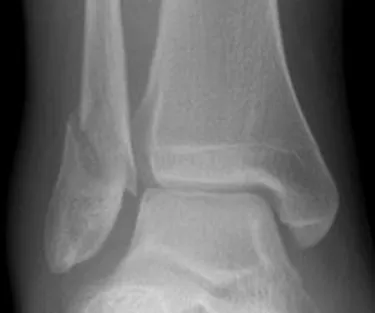

حبل الرباط المتلازمي / زر الغرزة: تثبيت الكاحل المتقدم والتعافي

مفصل الكاحل هو تحفة من الهندسة البشرية، يتيح نطاقًا واسعًا من الحركة ويتحمل أحمالًا كبيرة. في صميم استقراره تكمن أربطة المتلازمة (Syndesmotic ligaments)، وهي مجموعة من الأنسجة الليفية القوية التي تربط الأطراف السفلية لعظم الساق (الظنبوب) وعظم الشظية (الشظية). هذه الأربطة، التي تقع مباشرة فوق مفصل الكاحل، تشكل "نقرًا" (mortise) حاسمًا يثبت عظام الكاحل معًا، مما يسمح بالوظيفة الصحيحة.

تُعرف إصابة هذه الأربطة الحيوية عادةً باسم "التواء الكاحل العلوي"، ولكنها يمكن أن تتراوح من تمدد بسيط إلى تمزق كامل، وغالبًا ما تكون مصحوبة بكسر في الكاحل. على عكس التواءات الكاحل النموذجية، يمكن أن تكون إصابات المتلازمة أكثر خطورة، وتسبب إعاقة، وتستغرق وقتًا أطول للشفاء، مما قد يؤدي إلى عدم استقرار مزمن وألم إذا لم يتم علاجها بشكل صحيح.

لعقود من الزمن، كان العلاج الجراحي لإصابات المتلازمة غير المستقرة يتضمن غالبًا وضع مسامير مباشرة عبر الظنبوب والشظية لتثبيتهما معًا. على الرغم من فعاليته، كان لهذه الطريقة التقليدية قيود، تتمثل أساسًا في إنشاء تثبيت صلب يحد من حركة الكاحل الطبيعية وغالبًا ما يتطلب جراحة ثانية لإزالة المسامير بمجرد حدوث الشفاء.

هنا يأتي نظام حبل الرباط المتلازمي / زر الغرزة (Syndesmosis TightRope / Suture Button) – وهو تقدم ثوري في جراحة العظام. يوفر هذا الجهاز المبتكر حلاً ديناميكيًا ومرنًا لتثبيت المتلازمة، محاكيًا الحركة الطبيعية للأربطة مع تثبيت العظام بإحكام في مكانها. إنه يمثل تحولًا نموذجيًا، ويوفر للمرضى تعافيًا أسرع وأكثر راحة وغالبًا ما يلغي الحاجة إلى جراحة ثانية.